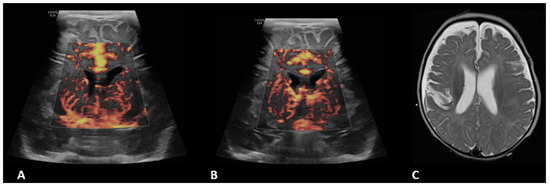

- Hwang, M.; Haddad, S.; Tierradentro-Garcia, L.O.; Alves, C.A.; Taylor, G.A.; Darge, K. Current understanding and future potential applications of cerebral microvascular imaging in infants. Br. J. Radiol. 2022, 95, 20211051. [Google Scholar] [CrossRef] [PubMed]

- Svrckova, P.; Meshaka, R.; Holtrup, M.; Aramburo, A.; Mankad, K.; Kazmi, F.; Owens, C.M.; Gala-Peralta, S.; Semple, T. Imaging of cerebral complications of extracorporeal membrane oxygenation in infants with congenital heart disease—Ultrasound with multimodality correlation. Pediatr. Radiol. 2020, 50, 997–1009. [Google Scholar] [CrossRef] [PubMed]

| Engorgement (n = 9) | 4/15 (26.7%) | 0.69 | 7/17 (41.2%) | 0.13 | 1/3 (33.3%) | 0.89 | 2/7 (28.6%) | 0.93 | 3/7 (42.9%) | 0.39 | 2/3 (66.6%) | 0.14 |

| Hypoperfusion (n = 12) | 6/15 (40%) | 1 | 7/17 (41.2%) | 0.88 | 1/3 (33.3%) | 0.80 | 3/7 (42.9%) | 0.86 | 3/7 (42.9%) | 0.86 | 1/3 (33.3%) | 0.80 |